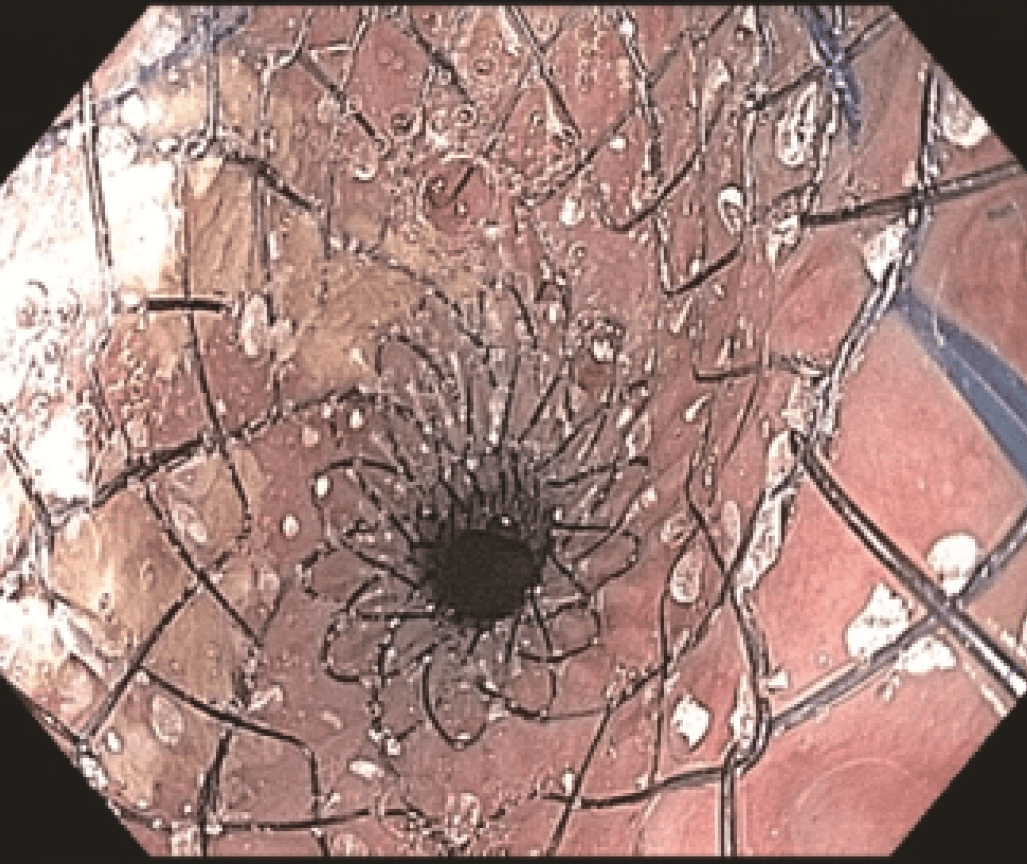

Endoscopic evaluation identified a stricture located at the proximal end of the SEMS (Figures 3 and 4) at 20 cm from the incisors, apparently caused by tumor growth. The upper esophageal sphincter was located at 16 cm from the incisors.

The stricture was located at the uncovered proximal end of the initial SEMS, placed at the cervical esophagus. The stricture was hard and did not allow the passage of the 4.9 mm scope.

However, the three marks at the HANAROSTENT’s distal, medial and proximal ends were easily seen under fluoroscopic guidance, and were valuable in ensuring acurate deployment, just distal to the upper esophageal sphincter (Figure 5). The distal end of the HANAROSTENT remained in the patent portion of the previous stent. The endoscopic view of the SEMS proximal end can be observed in the images below (Figures 6, 7 and 8).